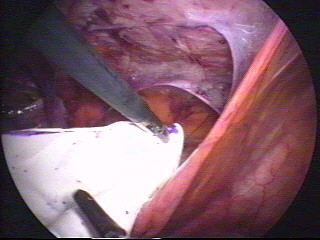

Herniorrafia laparoscópica